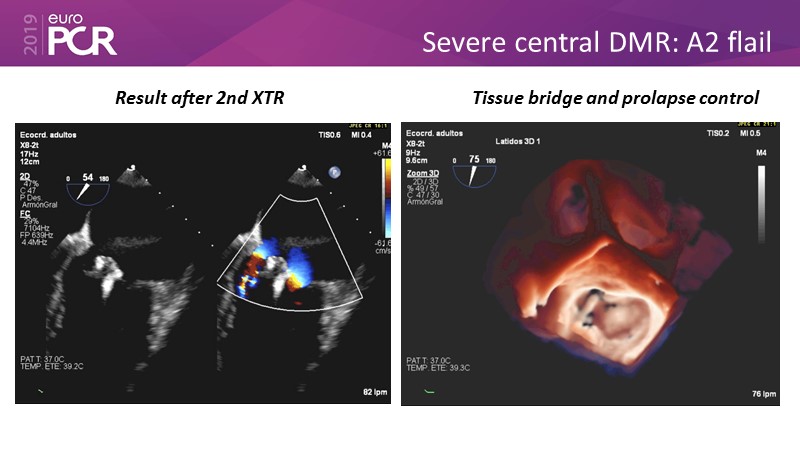

- To learn how will product innovation (Mitraclip NTR / XTR) drive improvement in procedural and clinical outcomes (EXPAND)